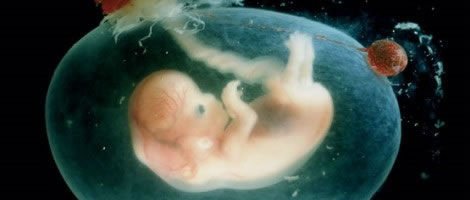

Durante a gravidez o embrião sofre uma serie de mudanças, já que passa de zigoto (embrião de uma só célula) à bebé, uma pessoa completamente formada com todos os órgãos internos. Este período é denominado de desenvolvimento embrionário.

O primeiro mês de gravidez é o mês no qual dá-se a fertilização, isto é, o óvulo é fertilizado pelo espermatozóide e o processo de formação do embrião inicia-se. Como é quase impossível detectar com exactidão o momento da fertilização, considera-se que o primeiro dia de gravidez é o primeiro dia da última menstruação. Assim, a primeira semana de gestação coincide com a última semana da menstruação.

O óvulo já fertilizado prossegue o seu caminho até ao útero. Durante esta descida, o núcleo do espermatozóide, que contém o material genético do homem, e o núcleo do óvulo, que contem o material genético da mulher, fundem-se e definem os genes do futuro bebé.